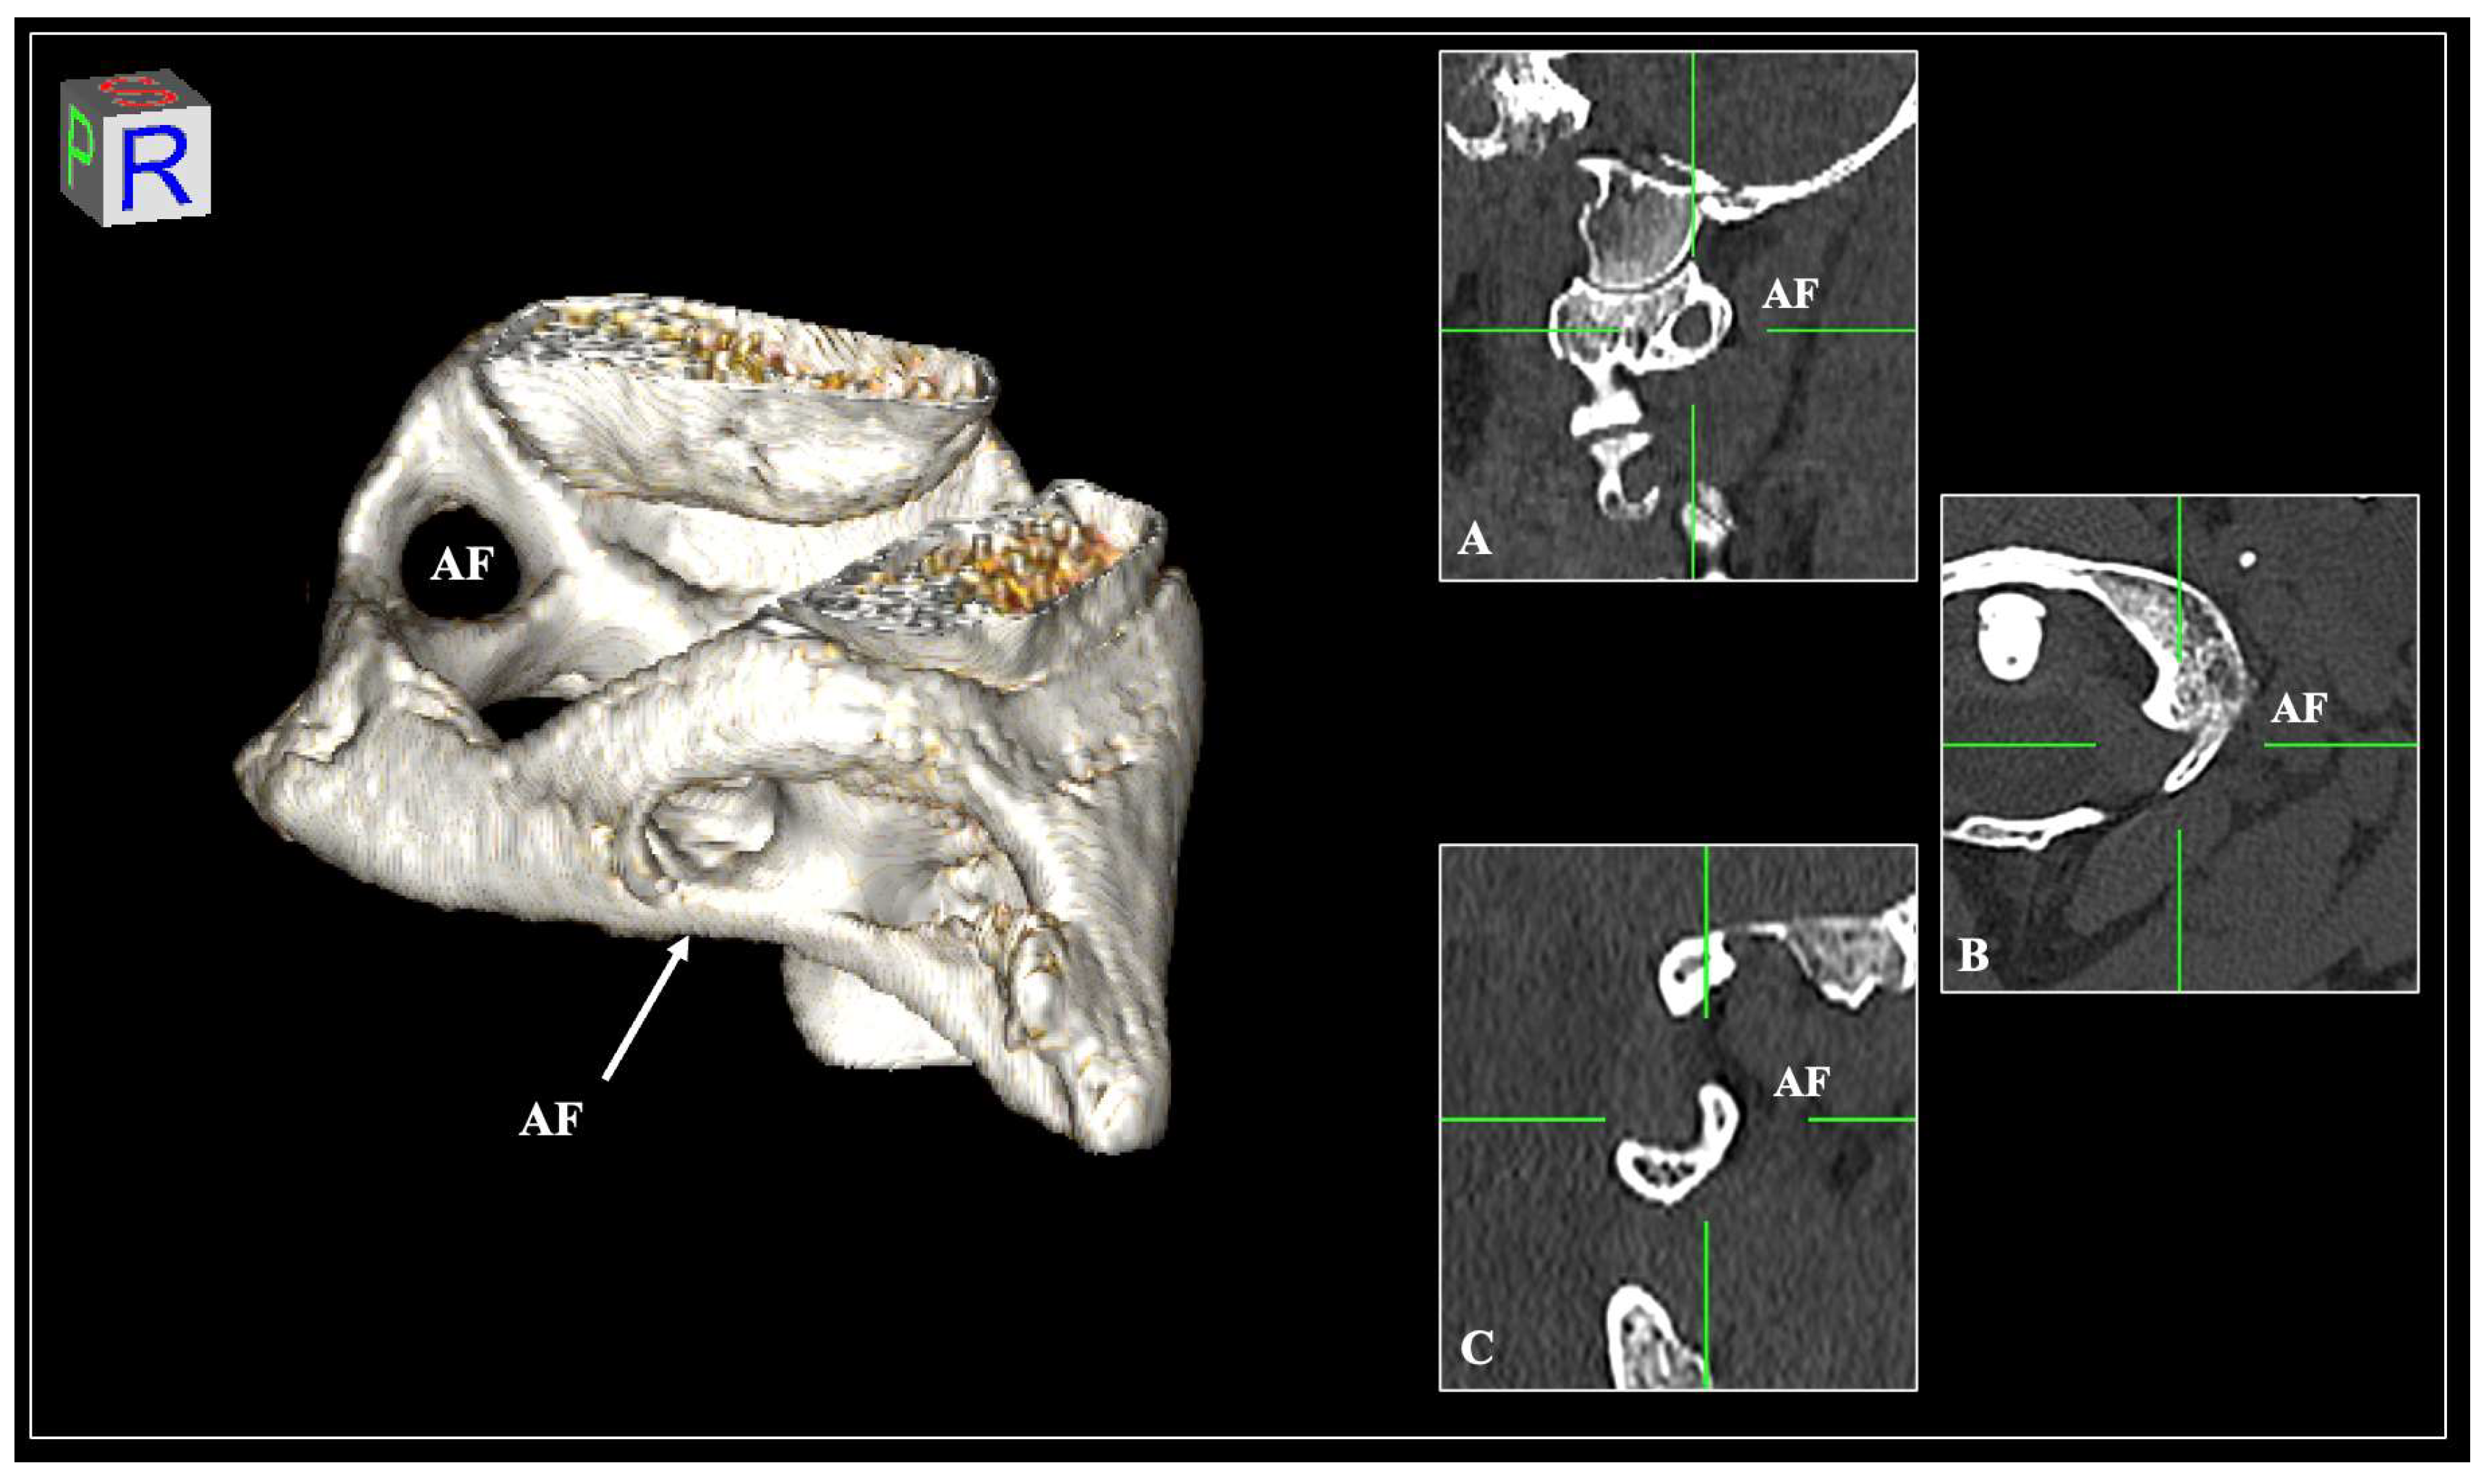

2. Materials and Methods

3. Results

4. Discussion